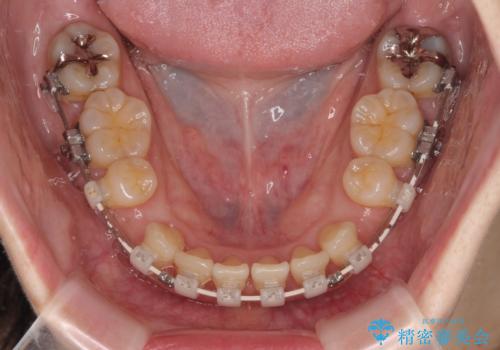

- 矯正装置

- 審美装置

- 前歯のデコボコと口元の突出感を気にして来院された患者様です。

上下前歯がくちばしのように突出していたため、上下左右の第一小臼歯4本を抜歯し、ワイヤー装置にて矯正治療を行うこととしました。

上顎骨に対して下顎骨がやや前方位に位置しているため、歯肉退縮を回避するために下顎前歯をあまり内側に移動させることができない状況でしたが、十分に口元の突出感を改善することができました。